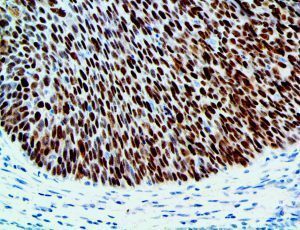

It is the ICU physician who is most likely to witness one of the deadliest manifestations of the abnormal immunological response, the cytokine storm syndrome (CSS). This response is also referred to by some as the cytokine release syndrome (CRS). CSS is characterized by continuous activation and expansion of macrophage and lymphocyte populations, which secrete large amounts of cytokines, causing the cytokine storm. This massive cytokine release is akin to hemophagocytic lymphohistiocytosis (HLH) disease, a syndrome characterized by initial unchecked and persistent activation of cytotoxic T lymphocytes and NK cells.

Clinical and laboratory manifestations of HLH include fever, enlarged liver and/or spleen, neurologic dysfunction, coagulopathy, liver dysfunction, cytopenias (i.e., low levels of erythrocytes, leukocytes, and/or platelets), hypertriglyceridemia, hyperferritinemia, hemophagocytosis, and eventually diminished NK cell activity as the immune system becomes progressively paralyzed. HLH can be familial (primary HLH) or secondary to another disease process (sHLH), such as rheumatic disease, in which it is referred to as macrophage activation syndrome (MAS, characterized by elevated ferritin).